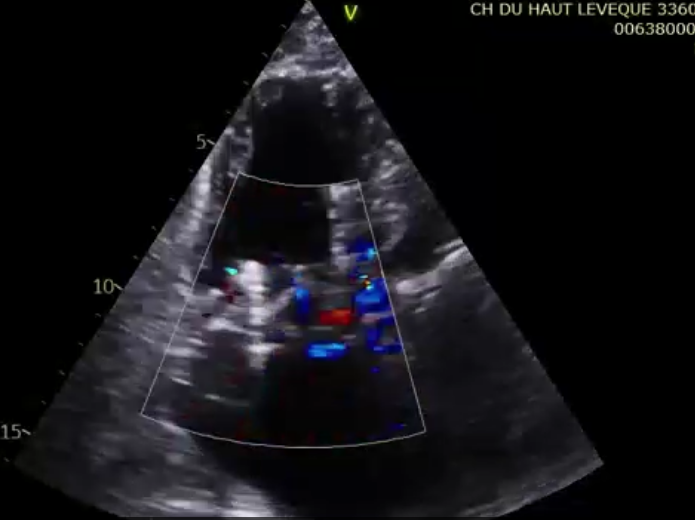

第二名患者是一位79歲的女性,術(shù)前TTE診斷TR等級4+,既往有高血壓、腎功能不全、肺動(dòng)脈高壓的病史。術(shù)者在擁有第一臺手術(shù)的經(jīng)驗(yàn)后,在TEE和DSA的引導(dǎo)下非常順利地完成瓣膜的釋放,術(shù)后瓣膜形態(tài)穩(wěn)定,TEE提示即刻反流0+?;颊咝g(shù)后七天TTE復(fù)查提示無明顯三尖瓣反流,瓣膜整體形態(tài)非常穩(wěn)定。

術(shù)后超聲提示微量瓣周漏